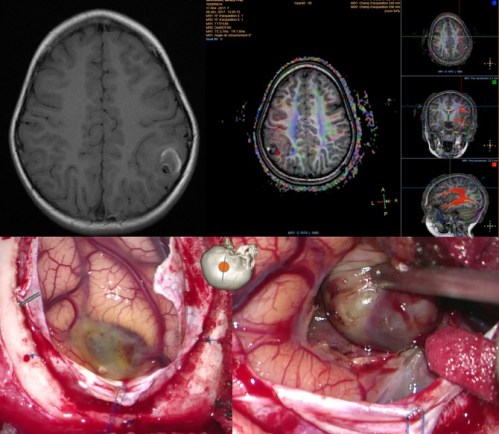

la neuronavigation est très utile dans les tumeurs de la convexité, surtout de petite taille et à proximité de la région centrale ; il est illusoire de vouloir reconnaitre les sillons corticaux, surtout lorsque l’anatomie est modifiée par la tumeur. par ailleurs l’imagerie peut être trompeuse en faisant croire que la tumeur sera visible dès l’ouverture durale alors qu’elle est sous-corticale. inversement, la neuronavigation n’est pas indispensable lorsqu’il existe des repères anatomiques fiables : suture coronale, vallée sylvienne, sillon péri-calleux, structures de la base.

la neuronavigation est par contre particulièrement précieuse dans cette région.